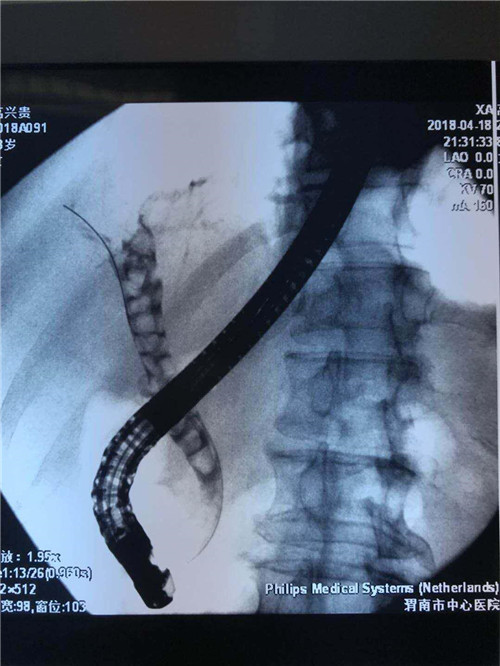

曹鹏医生进十二指肠镜后看到肿大的乳头,利用切开刀+导丝超选进入胆管,行十二指肠乳头切开,随即大量脓性胆汁流出,并迅速留置鼻胆管。功夫不负有心人,终于,在主管护师许晓庆、护士王欣的配合下,又成功挽救了一名病患的生命,同时也彰显了市中心医院消化内镜中心医护人员极高的专业素养和娴熟的业务能力。